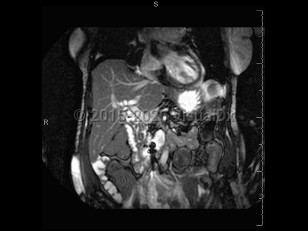

Abdominal aortic aneurysmAbdominal aortic aneurysm

Intraabdominal abscessIntraabdominal abscess

Pyogenic liver abscessPyogenic liver abscess